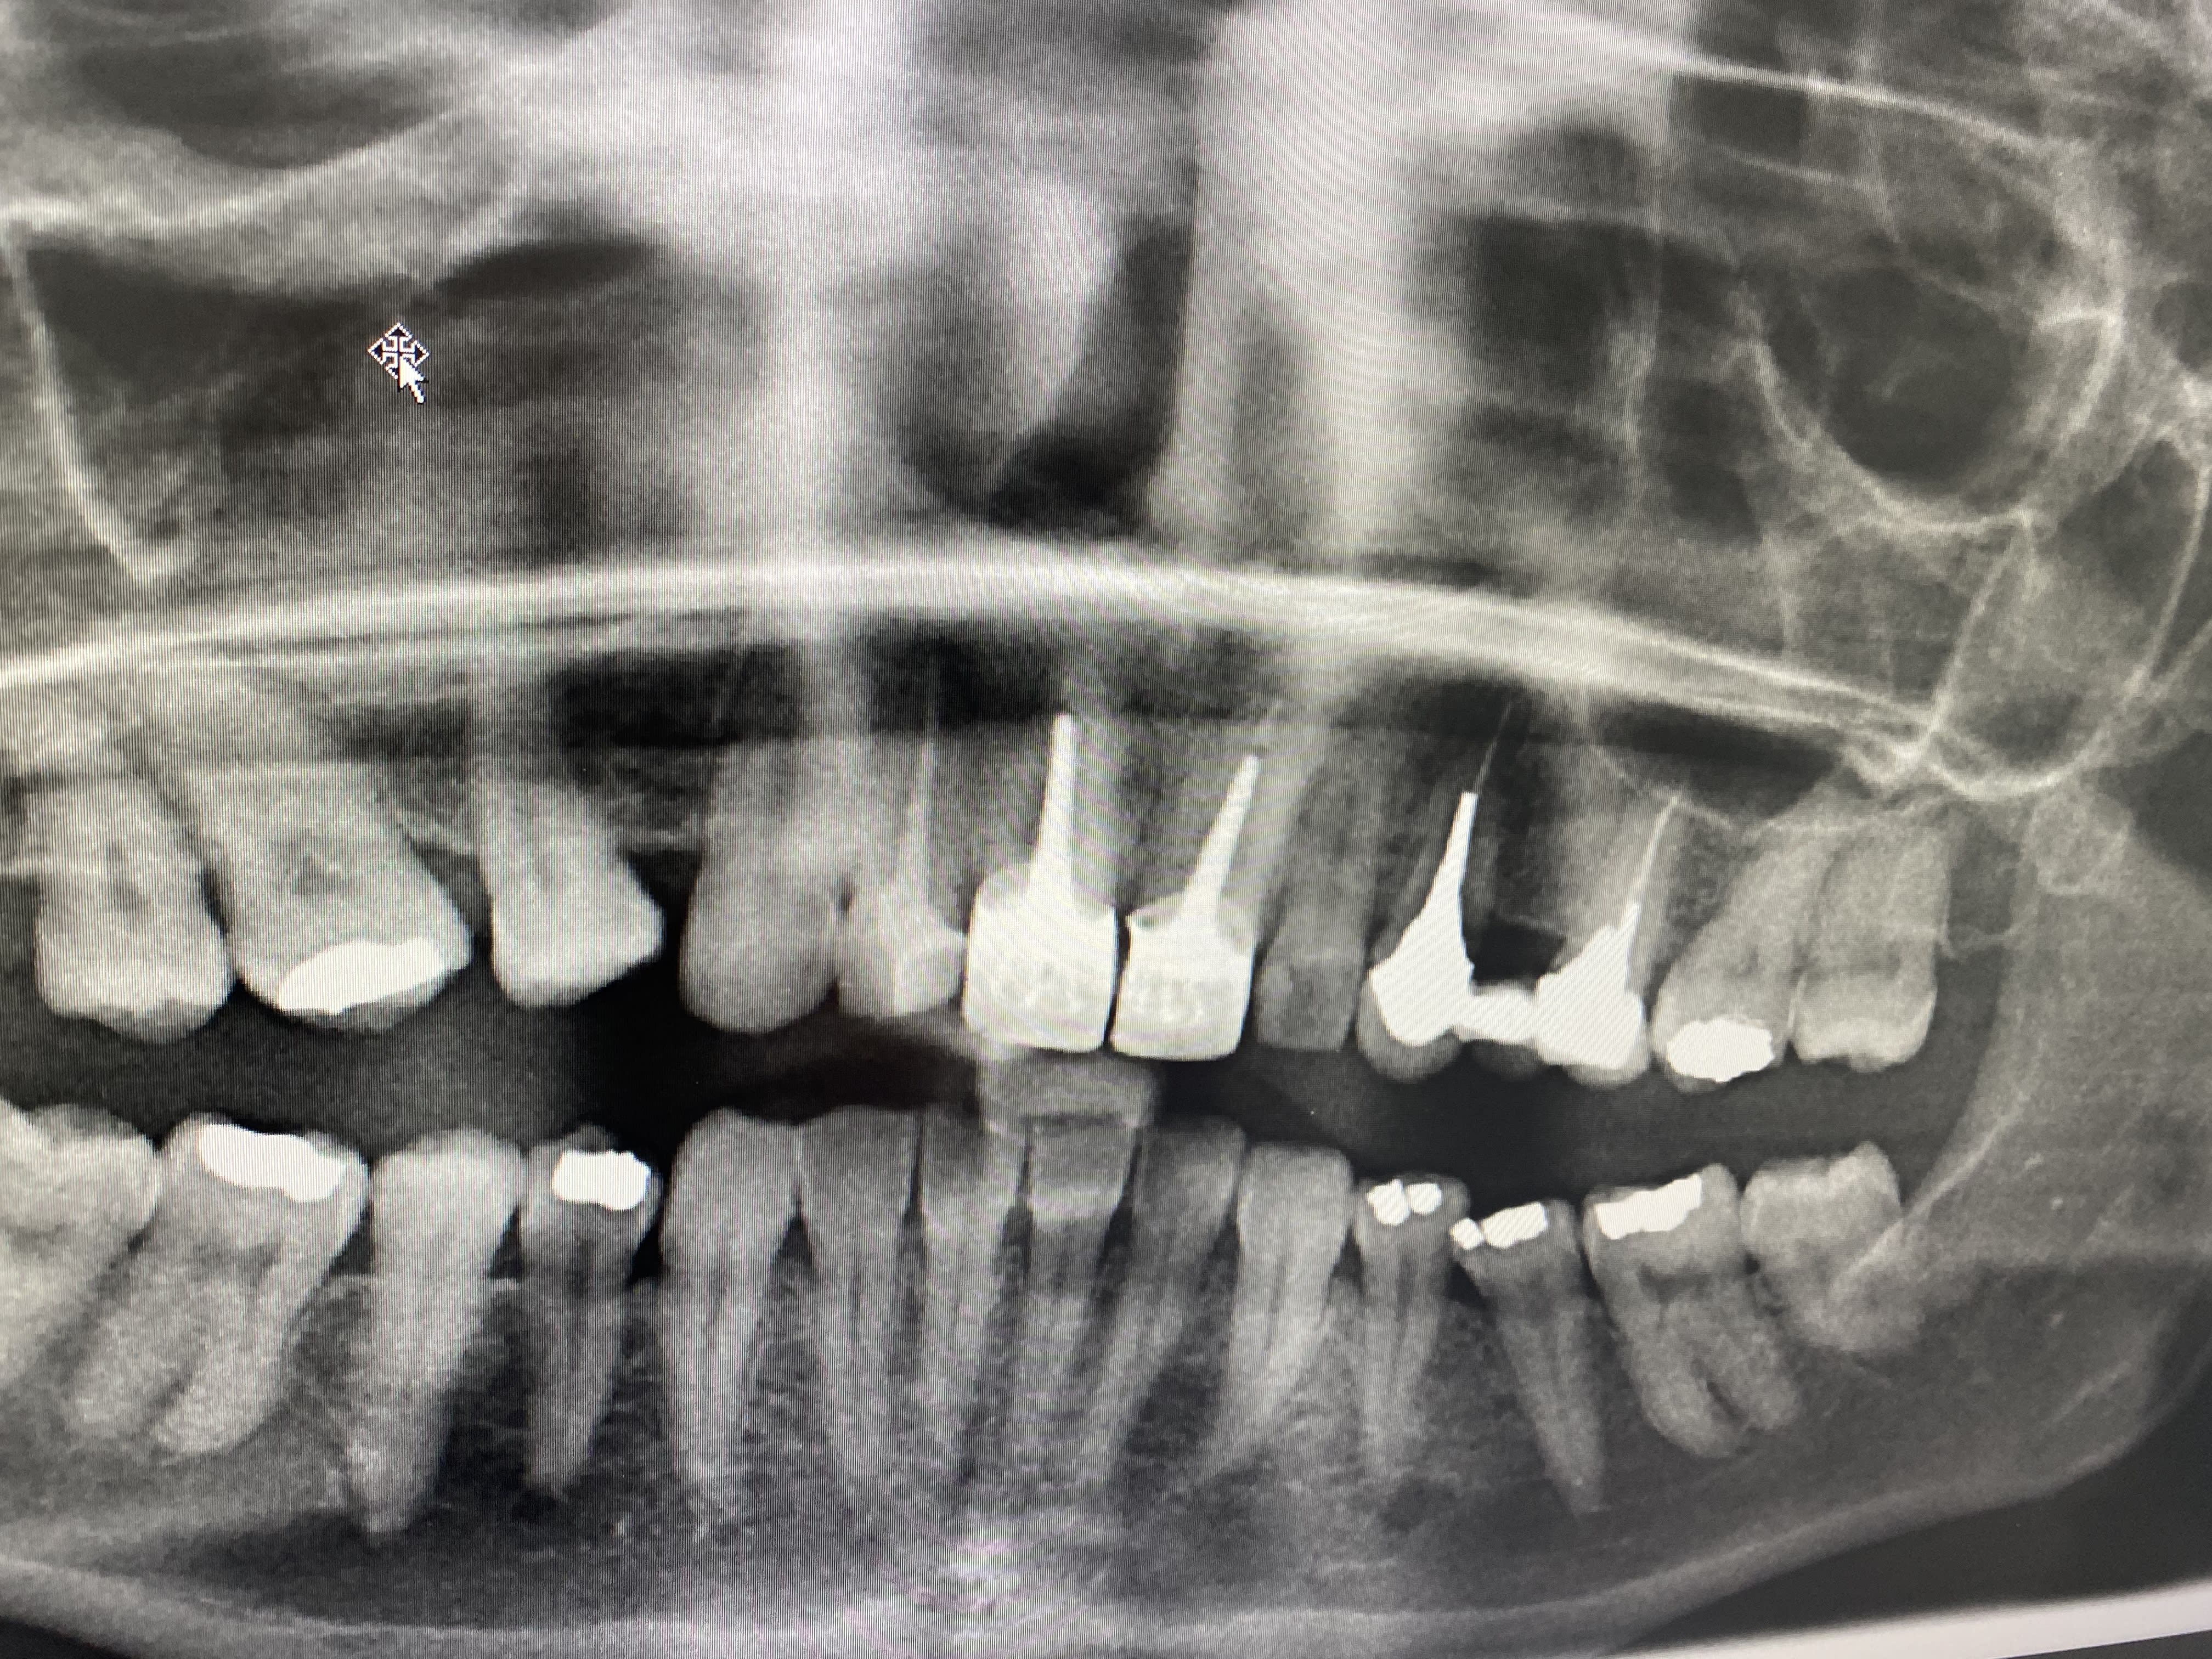

Cas dont je suis fier, et qui m'énerve un peu.

Patiente que j'ai vaguement vue en 2019 pour 3 bricoles, rien de notable.

Un peu après le premier confinement (05 2020 donc), commence à ressentir des douleurs diffuses maxillo faciales; son généraliste lui prescrit des antibiotiques pour une sinusite.

Rebelote 6 mois plus tard, cette fois elle se rend aux urgences dentaires, qui ne voient rien et la renvoient vers un orl.

L'orl la voit, lui fait faire une irm, diagnostique un quelconque SADAM ou équivalent, lui prescrit de la gymnastique mandibulaire et , coup de chance en fait, lui dit d'aller voir ma gueule pour faire une gouttière.

Entre temps, re "sinusite", re antibios, re soulagement temporaire.

Bref, elle arrive ce soir pour une consult occluso/gouttière, et heureusement que je ne fais pas trop confiance à personne, je reprends tout du début.

Evidemment, aucun signe douloureux musculaire, ATM parfaitement fonctionnelles, mais une 37 qui ne réagit ni au froid, ni au fraisage, et finalement ni à l'ouverture de chambre.

1 an que ça durait ces conneries, pour un diag simplissime, ça pique toujours un peu. A mon avis, ça va vite aller mieux. On verra hein?